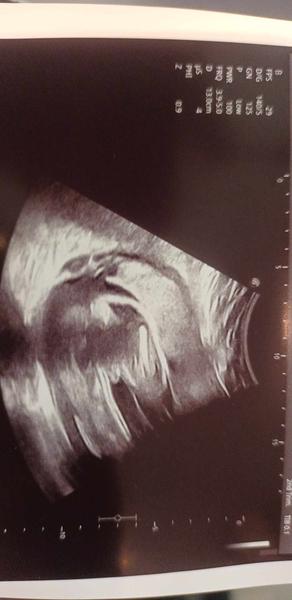

Zkušenosti a názory na pohlaví dítěte ve 25. týdnu?

Mám dva kluky a tipuju, že ty taky čekáš kluka - měli jsme podobné fotky ☺️ během vyšetření ti lékař neříkal?

@pipi_puncocha jj říkali, že na 80 % kluk , a tohle už je druhá fotka podobná.. tak snad to ten kluk bude 🙂

Kluk